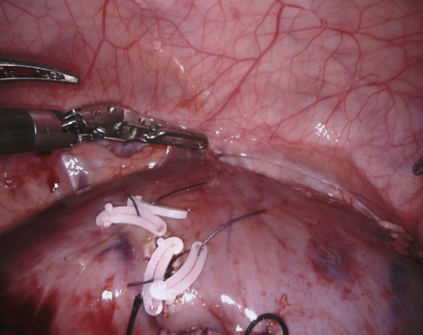

DeepSeek series have demonstrated outstanding performance in general scene understanding, question-answering (QA), and text generation tasks, owing to its efficient training paradigm and strong reasoning capabilities. In this study, we investigate the dialogue capabilities of the DeepSeek model in robotic surgery scenarios, focusing on tasks such as Single Phrase QA, Visual QA, and Detailed Description. The Single Phrase QA tasks further include sub-tasks such as surgical instrument recognition, action understanding, and spatial position analysis. We conduct extensive evaluations using publicly available datasets, including EndoVis18 and CholecT50, along with their corresponding dialogue data. Our comprehensive evaluation results indicate that, when provided with specific prompts, DeepSeek-V3 performs well in surgical instrument and tissue recognition tasks However, DeepSeek-V3 exhibits significant limitations in spatial position analysis and struggles to understand surgical actions accurately. Additionally, our findings reveal that, under general prompts, DeepSeek-V3 lacks the ability to effectively analyze global surgical concepts and fails to provide detailed insights into surgical scenarios. Based on our observations, we argue that the DeepSeek-V3 is not ready for vision-language tasks in surgical contexts without fine-tuning on surgery-specific datasets.